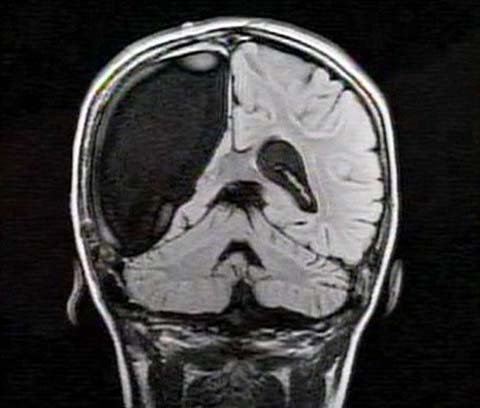

中新網(wǎng)3月26日電 據(jù)英國(guó)媒體26日?qǐng)?bào)道,一名9歲的英國(guó)女孩在經(jīng)歷了右腦切除手術(shù)后奇跡康復(fù),令醫(yī)生和家人無(wú)比震驚。

報(bào)道稱(chēng),現(xiàn)年9歲的卡梅倫·莫特在手術(shù)中切除了她整個(gè)右半邊的大腦,而在經(jīng)歷如此重大的手術(shù)后能迅速康復(fù),莫特的奇跡也讓醫(yī)生和她的家人驚嘆不已。年幼的莫特也沒(méi)有因?yàn)椴“Y而放棄對(duì)夢(mèng)想的追求。

卡梅倫莫特在3歲那年患上一種被稱(chēng)作大腦功能紊亂“拉斯穆森”綜合癥,這種病癥誘發(fā)患者的無(wú)序暴力行為和嚴(yán)重的癲癇。醫(yī)生建議,治療這種病癥只能通過(guò)嘗試消除引發(fā)此癥狀的大腦組織。而手術(shù)讓莫特失去了幾乎整個(gè)半邊的大腦。

據(jù)悉,莫特在手術(shù)后已經(jīng)可以跑動(dòng)和玩耍,她在術(shù)后的第四周離開(kāi)了醫(yī)院。醫(yī)生表示,雖然右半邊大腦的切除可能會(huì)給莫特帶來(lái)半身不遂的風(fēng)險(xiǎn),但孩子剩余的大腦仍具有很強(qiáng)的重組和布線能力。